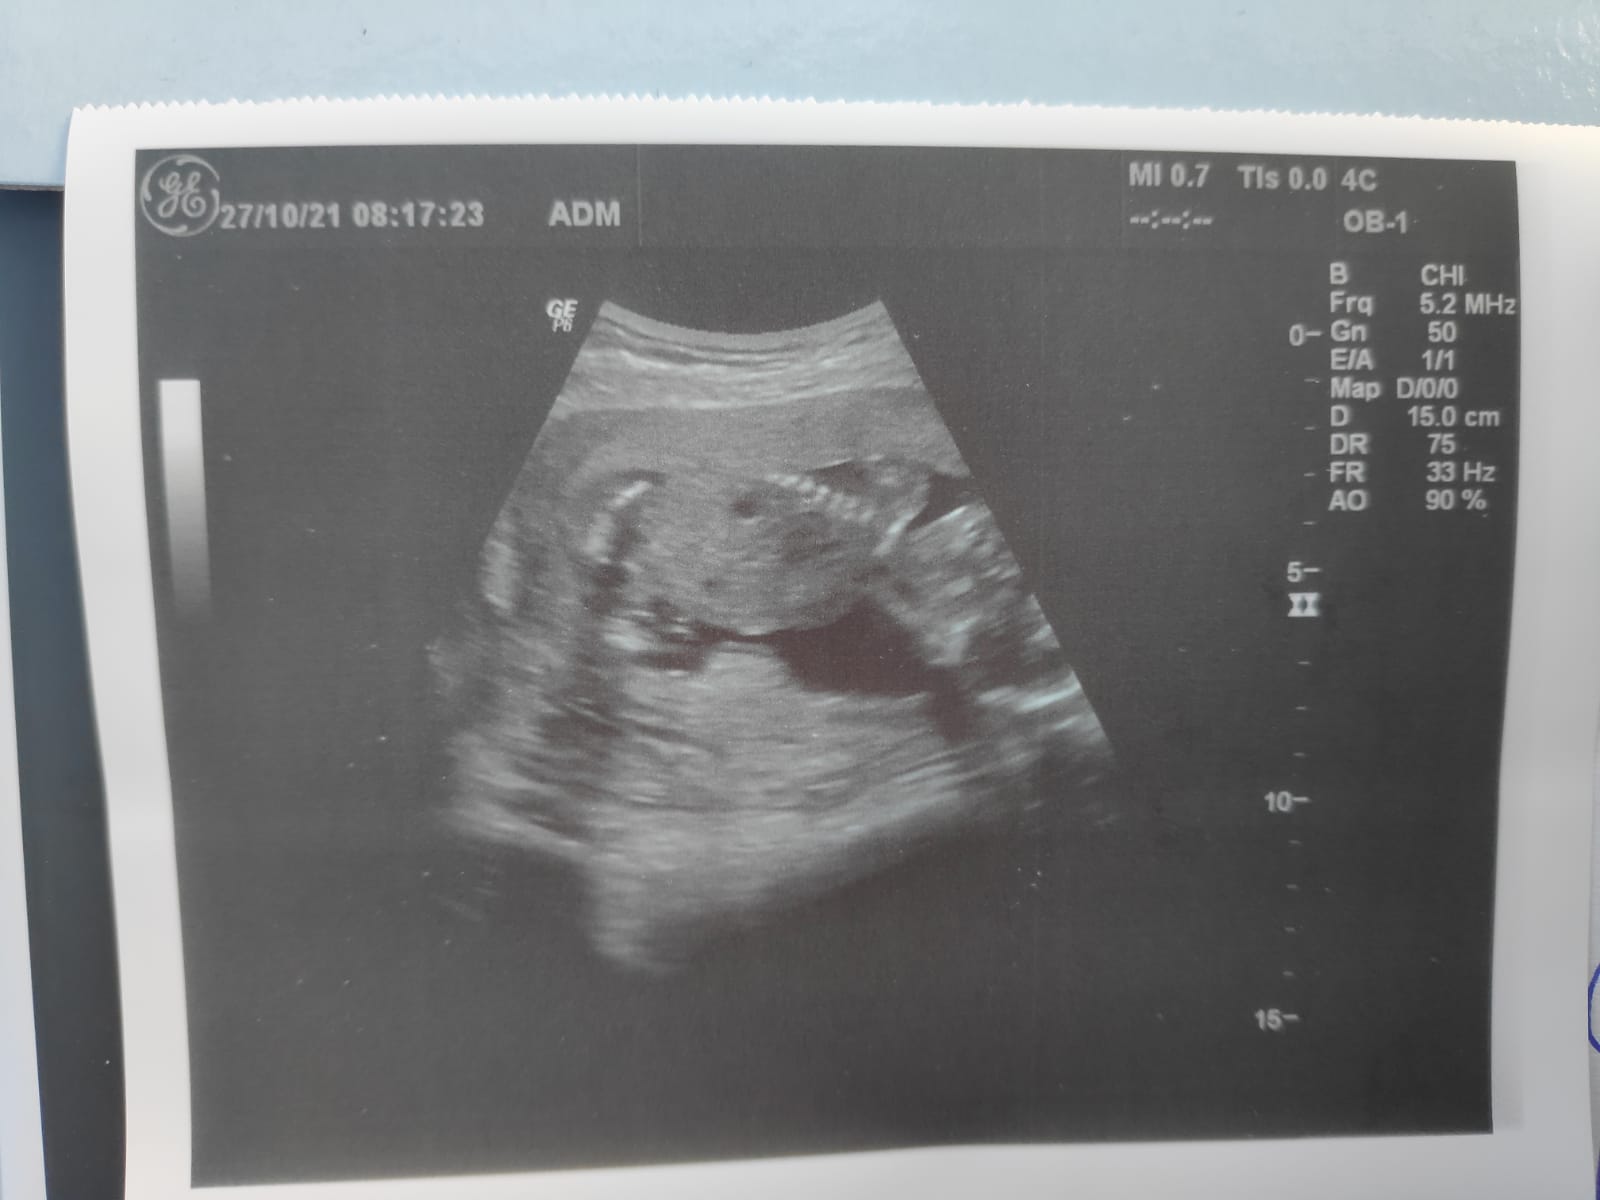

I co ? chłopczyk ?Witam, czy na podstawie tych zdjęć usg można rozpoznać płeć?

jestem tu nowa i dopiero poznaję forum. Nie wiem, czy w dobrym miejscu to zamieszczam, ale czy coś z tego USG widać co do płci?